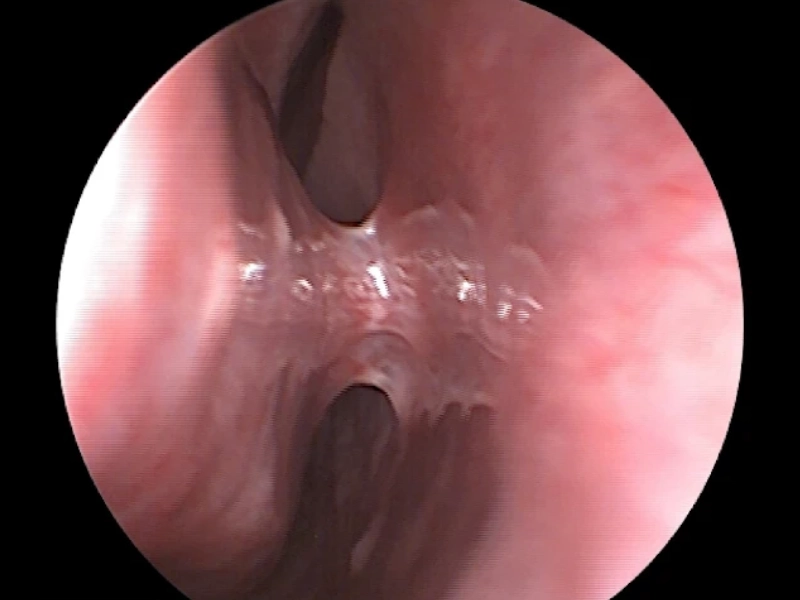

علائم چسبندگی بینی چیست و چگونه درمان میشود؟

چسبندگی بینی زمانی ایجاد میشود که بافتهای داخلی بینی بعد از جراحی یا آسیب به یکدیگر بچسبند و جریان طبیعی هوا را محدود کنند. این